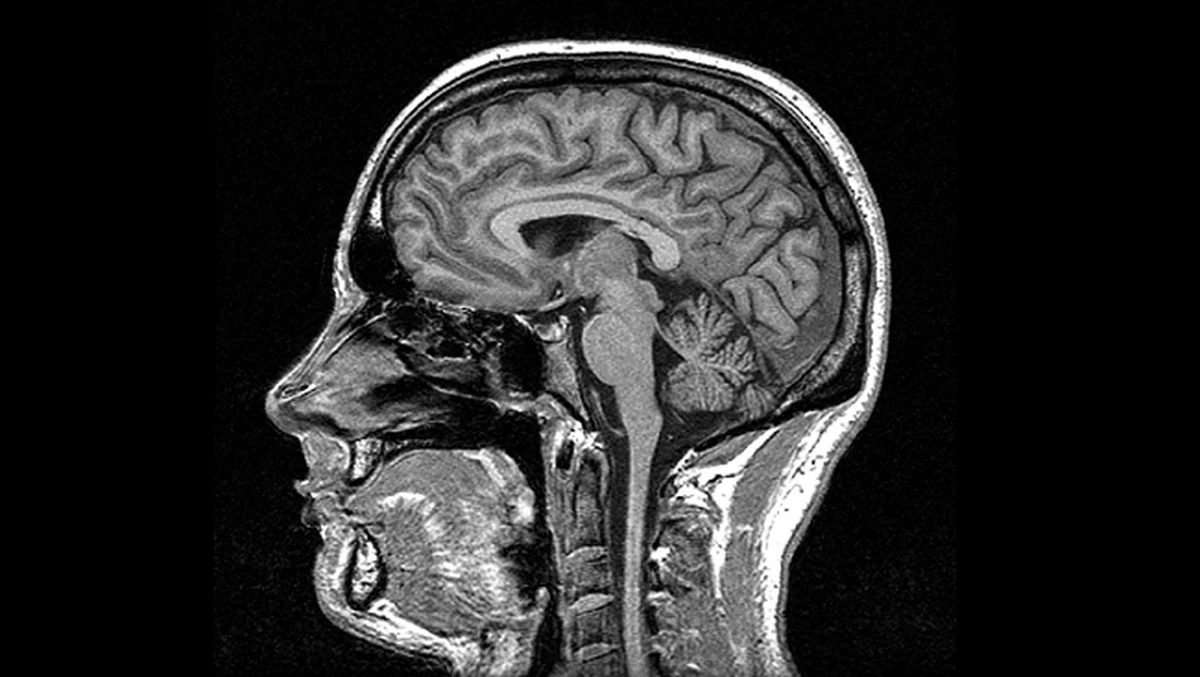

Najnowsze badania sugerują, że klucz do regulacji ciśnienia krwi może znajdować się w małym obszarze mózgu, o którym rzadko się mówi. To odkrycie może zmienić sposób, w jaki podchodzimy do zdrowia układu krwionośnego w najbliższych latach.

Zespół naukowców z Brazylii i Nowej Zelandii skupił się na regionie mózgu zwanym lateral parafacial (pFL). Do tej pory kojarzono go głównie z kontrolą oddechu – z tymi momentami, gdy bierzesz głębszy oddech podczas ćwiczeń lub gdy kaszlesz.

Okazuje się jednak, że ten sam obszar potrafi działać jak ukryty hamulec bezpieczeństwa dla twoich naczyń krwionośnych. Kiedy pFL staje się zbyt aktywne, wysyła sygnał do organizmu, by „zacisnąć” naczynia, co bezpośrednio przekłada się na skok ciśnienia.